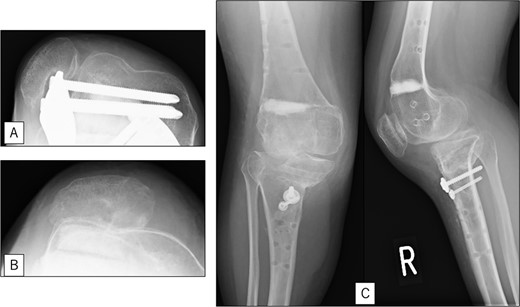

A 23-year-old woman presented with bilateral knee pain and gait abnormalities owing to marked lower extremity deformity. She was diagnosed with EVC as a child but had never been followed up by orthopedics because she was not in pain. On physical examination, marked valgus instability was observed in both knees, and the motion of both knees ranged from 10° to 135°. Radiographic examinations of both knees, including computed tomography, showed valgus deformity, lateral and anterior depression of the proximal lateral tibial plateau, and external rotation deformity of the lower leg. Patellar dislocation was observed in the right knee (Fig. 1). The radiological angles are presented in Table 1. The right knee underwent surgery first, followed by the left 10 months later. Lateral and medial skin incisions were made. Extensive lateral retinacular release, fractional lengthening of the distal lateral hamstring, and Z-lengthening of the iliotibial band were then performed. At this stage, peroneal nerve strain was identified, and decompression of the peroneal nerve was performed. Osteotomy was subsequently performed on the tibia. Closed-wedge varus and derotational osteotomy of the proximal tibia and open-wedge varus osteotomy of the distal femoral varus were performed. In addition, vastus medialis advancement was performed on the right knee, and patellar realignment was achieved in extension (Fig. 2). However, the knee showed a subluxation tendency owing to flexion of >30°; therefore, the postoperative rehabilitation plan progressed more slowly than that of the left knee. Range of motion training began on the left knee immediately after surgery without any restrictions, but on the right knee only after 3 weeks of postoperative immobilization in the extended position. However, ambulation exercise was performed on both knees with no loading for 3 weeks, then partial loading was initiated, and full loading was permitted at 8 weeks postoperatively. Early postoperative standing radiography showed residual mild valgus deformity of the lower limbs (Fig. 2, Table 2). In addition, the right knee showed patellar re-dislocation 2 months postoperatively, and the patellar deformity gradually progressed owing to the femoral implant; therefore, the patient underwent implant removal, tibial tubercle transfer, and medial patellofemoral ligament reconstruction 1.5 years after the initial surgery (Fig. 3). Six months later, she fell while walking and developed a fracture at the osteotomy of the right femur; open reduction and internal fixation were performed (Fig. 4). The remaining years passed uneventfully, and 10 years after the initial surgery, the patient still had mild valgus deformity of the lower limbs, but had no recurrence other than that experienced immediately after surgery, no complaints of knee pain, and a stable gait (Fig. 5, Table 2).

Preoperative radiography and computed tomography: (A) anteroposterior and lateral views of the right knee, (B) skyline view of the right knee, (C) anteroposterior and lateral views of the left knee, (D) skyline view of the left knee, (E) standing anteroposterior view, and (F) 3D image of the entire lower limb.